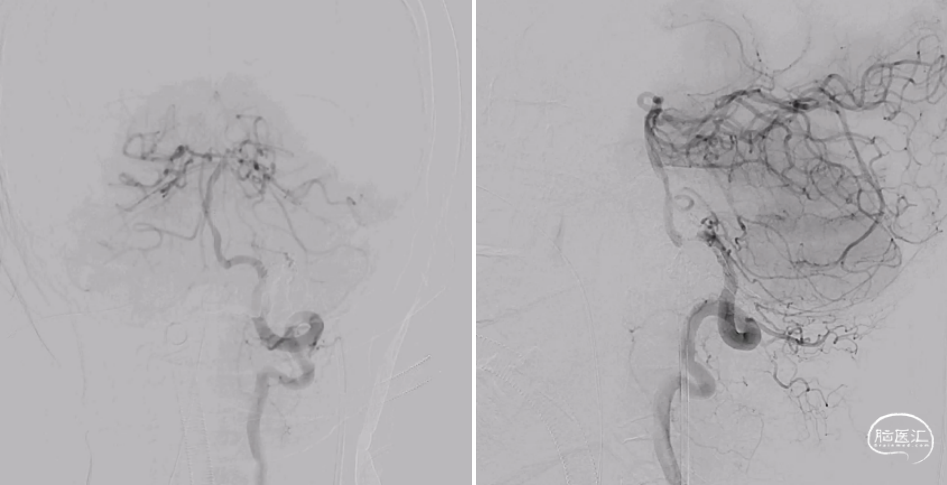

根据病史及当地医院辅助检查,诊断后颅窝硬脑膜动静脉瘘明确。分析当地医院MRA及血管造影结果,大致可判断该患者瘘口位于左侧舌下神经管或髁前汇区。详细读片可见左侧颈外动脉造影及椎动脉造影所示引流模式相同。入院后完善脑血管造影检查,并应用双容积影像后处理技术进行三维重建(图3)。便于进一步分析血管构筑,制定手术策略。

根据患者术前血管造影表现,该例病例确诊为左侧舌下神经管区硬脑膜动静脉瘘。分析其血管构筑特点:供血动脉为颈外动脉咽升动脉分支,椎动脉脑膜支,瘘口位于左侧舌下神经管区,经岩下窦向同侧海绵窦-海绵间窦-对侧海绵窦引流,并经髁前静脉向椎旁及椎管内静脉引流。患者有显著的搏动性耳鸣症状,且引流静脉具有出血风险,手术指征存在。笔者所在的中心既往诊疗的病例表明,舌下神经管的引流模式多种多样,但多数可见髁前静脉向岩下窦汇合。该患者亦有此静脉引流通道(图3黄色箭头所示),因此介入栓塞的路径上可考虑经要岩下窦-髁静脉路径。

术中将导引导管置于左侧颈内静脉,并引导至左侧岩下窦,Echelon-10微导管经由髁静脉超选至瘘口处。微导管到位后再次进行双容积三维后处理,验证微导管到位位置为术前所判断的瘘口处(图4),随后在瘘口放置一枚弹簧圈,并在阴性路图下注入Onyx胶0.8ml(图5)。复查造影见瘘口完全栓塞,异常引流彻底消除(图6)。